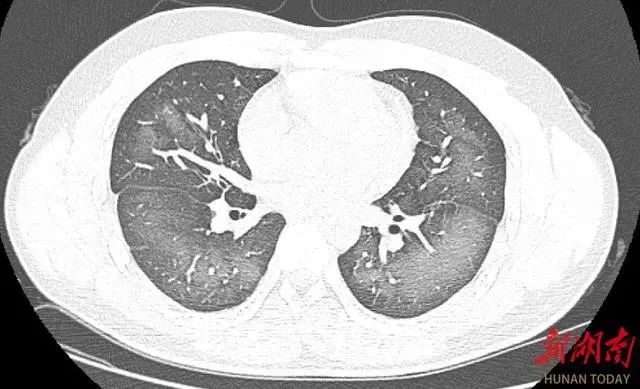

經(jīng)檢查,肺部CT片顯示,李林雙肺赫然呈現(xiàn)大范圍白色樣病變,報告提示“白肺”。

“白肺”一般是指重癥肺炎在X線或CT檢查下的表現(xiàn),患者肺部呈現(xiàn)一大片的白色狀態(tài),往往會出現(xiàn)呼吸困難、呼吸衰竭,嚴重者還會出現(xiàn)其他臟器功能障礙。“白肺”常見于高齡(65歲以上)、免疫力低下、有重要器官慢性病史(如心臟病、中風史、慢性腎臟病、慢性阻塞性肺疾病等)、有多種疾病并存(比如既有高血壓、糖尿病,又有心臟病、肺病、腎功能不全)等人群。